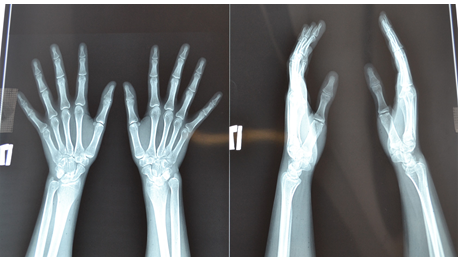

Рентгенография:

- Является основным и первым методом диагностики. Выполняется в двух проекциях (прямой и боковой), а иногда и в косых.

- Особенность рентгена при переломах зоны роста заключается в том, что хрящевая пластинка не видна на снимках, так как не задерживает рентгеновские лучи. Перелом определяется по смещению эпифиза, наличию метафизарного или эпифизарного фрагмента, расширению или неровности зоны роста.

- Часто для сравнения делают снимок здоровой конечности, особенно у маленьких детей, чтобы исключить естественные варианты строения или физиологические зоны роста, которые могут быть ошибочно приняты за перелом.

- Рентгенография позволяет определить тип перелома по классификации Солтера-Харриса (Salter-Harris).